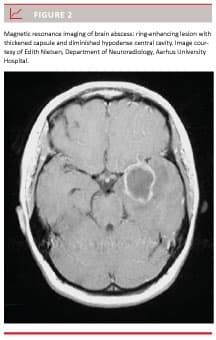

Acute otitis media (AOM) (Figure 1) is one of the most frequent paediatric diseases, but the condition may also occur among adults. Cholesteatoma is a much less common middle ear disease with onset in childhood or adulthood. Usually, the course of both AOM and cholesteatoma is benign, at least in developed countries with high socio-economic standards and easy access to health services [1]. However, due to the close anatomical proximity of the middle ear cleft and the brain, the infection can spread to intracranial structures, and otogenic meningitis or even brain abscess (BA) (Figure 2) may develop [1, 2].

The finding of a ring-enhancing lesion by CT with contrast or MRI is essential in confirming the OBA diagnosis. All the OBAs in the present study were confirmed with MRI. Differential diagnoses with ring-enhancing lesions are necrotic glioblastomas and cystic metastatic brain tumours. Distinction has improved by using diffusion-weighted MRI where Bas, as opposed to tumours, are indicated by hyperintensity [13, 14]